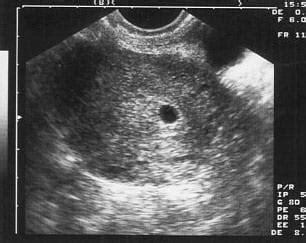

Az 5. hét végén a petezsák jelenik meg, ezt keresik a méhben, mert ez lesz a kis embriócsomó otthona. Az ultrahang képen ez egy jól körülhatárolt kis fekete folt lesz a szürkés színű háttérben. Megállapítják, hogy jó helyen található-e, nincs-e méhen kívüli terhesség.

A petezsák megjelenése és jellemzői

A petezsák egy jellegzetes, fekete vagy sötét, kerek, folyadékkal telt területként jelenik meg az ultrahang monitoron. Ezt a sötét területet egy vastag, világosabb, hiperechogén gyűrű veszi körül. Ez a gyűrű valójában a méh nyálkahártyájának (decidua) reakciója a beágyazódásra, és a trofoblaszt sejtek helyét jelzi. A kettős decidualis zsák jel (DDSS) megléte jelzi, hogy a beágyazódás sikeres volt, és a terhesség a méh megfelelő rétegében fejlődik.

A szakértő orvos számára a petezsák formája és elhelyezkedése is információt hordoz. Ideális esetben a petezsák kerek, sima kontúrú és a méh üregének felső részén (fundus) helyezkedik el. A szabálytalan, pl. lapos vagy könnycsepp alakú petezsák utalhat arra, hogy a méh nyálkahártyája nem képes megfelelően támasztani a fejlődő terhességet. Bár ez nem feltétlenül jelent rossz kimenetelt, gyakran összefüggésbe hozzák a magasabb vetélési kockázattal.